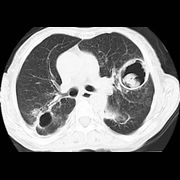

白肺的意思是指胸片、CT上发现正常肺组织透X线是黑色,只有心脏和大血管是白色,但是由于各种疾病、各种致病因素,导致两肺野呈大片的密度增高,出现白色的阴影,就...47600人收听

白肺一般是指重症肺炎在X光检查下的表现,肺部呈现一大片的白色状态而闻名。形成白肺一般都预示着肺部被炎症所广泛浸润,引起白肺的病因往往非常复杂,并且来势凶...28117人收听

白肺是指患者在X光胸片检查或者肺部CT检查中,肺部间质组织呈现大片状白色状病变的表现。白肺的症状表现多发生于重症肺炎,因为肺部间质组织持续性受到病毒、细...60057人收听

白肺(White lung)是一种临床综合症,其特征是重度肺炎患者的肺部积累了大量渗出物,影响多个肺叶,使肺部影像学检查呈现出大范围的白色区域。病因多为新型冠状病毒感染、细菌性肺炎、中东呼吸...

[最佳答案] 白肺是放射学名词,所谓白肺是指胸片或者CT上弥漫的高密度影,使得片子看不到肺纹理。导致白肺发生的原因很多,常见的大叶性肺炎、肺水肿,或者是病毒性肺炎比如SARS,以及流感、病毒引起的肺炎都会导致白肺。 至于能不能治愈要根据疾病的不同来决定, 白肺是放射学名词,所谓白肺是指胸片或者CT上弥漫的高密度影,使得片子看不到肺...